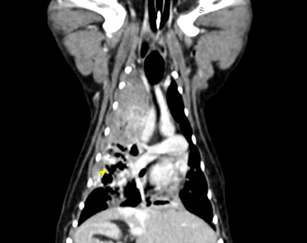

• 狗狗後腳癱瘓也有可能是血栓 不一定是骨骼神經肌肉問題喔

狗狗後腳癱瘓也有可能是血栓 不一定是骨骼神經肌肉問題喔